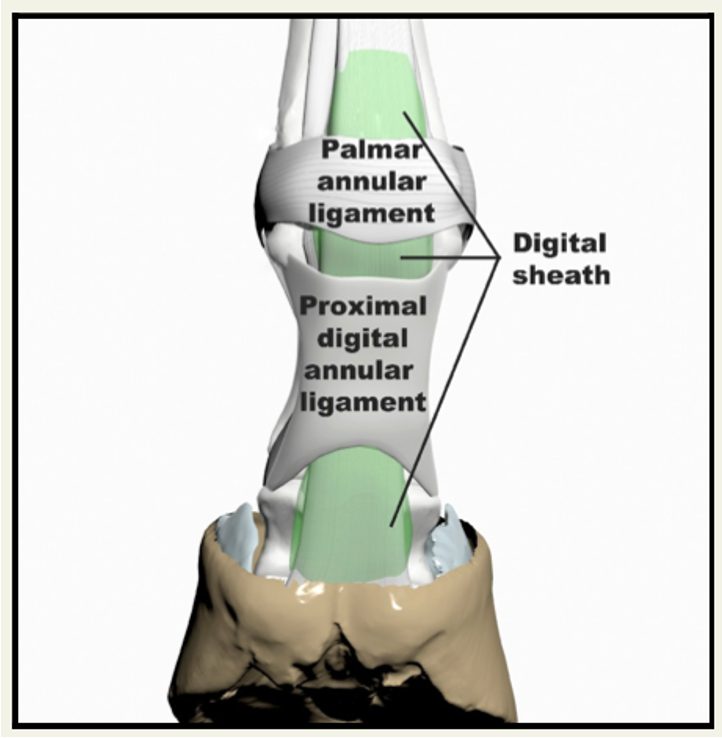

pressbooks.umn.eduAnnular Ligament

pressbooks.umn.eduAnnular Ligament

quizlet.comPart 4: Distal Thoracic Limb – Dissection Lab Guide For Ungulate Anatomy

quizlet.comPart 4: Distal Thoracic Limb – Dissection Lab Guide For Ungulate Anatomy